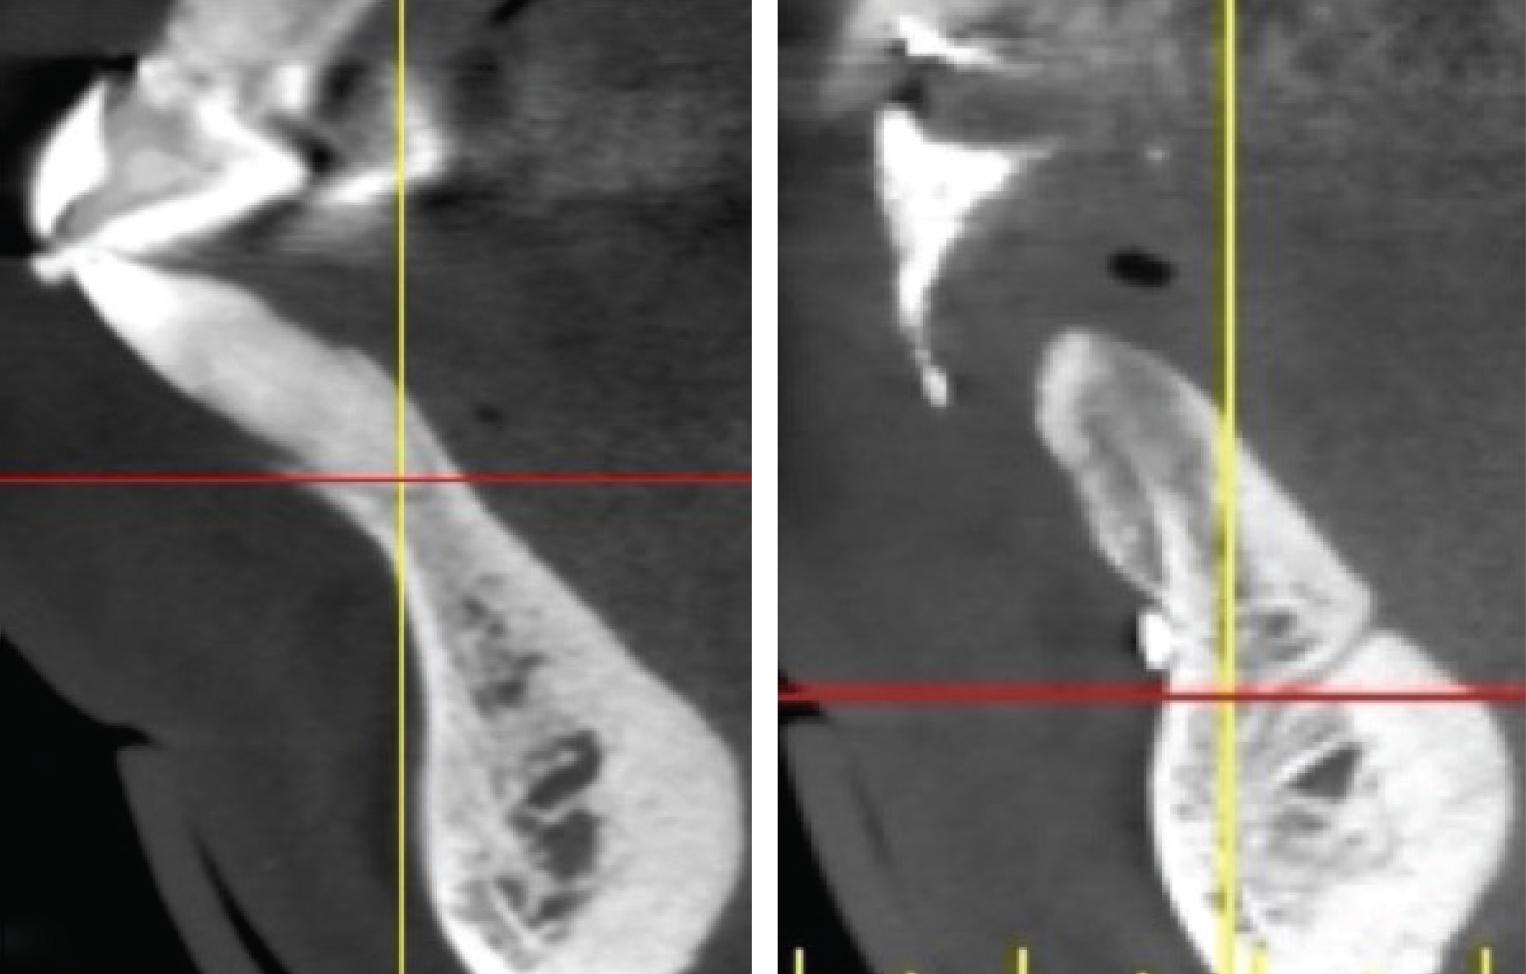

The shape and amount of bone present apical to the extraction socket is the apical topography and is important in treatment planning for both immediate and delayed implant placement. For immediate implant placement, the apical topography is significant, as 3 mm to 4 mm of native bone needs to be engaged for primary stability of the implant.1,2 If planning a 2-stage approach with site preservation and delayed implant placement, analysis of the apical topography is also essential. If a tooth with an apical concavity is extracted and a graft is placed only inside the socket, there may not be adequate bone following healing to place the implant in the proper position without additional surgical procedures3 (Figure 2). Teeth that do not have enough apical bone to provide the housing necessary for immediate implant placement or delayed implant placement with grafting inside the socket alone are defined as having inadequate apical topography. This inadequacy can be the result of periapical pathologies or the anatomy of the alveolus.

Imagery depicting examples of single-rooted sockets showing periodontium status, socket conditions, and CBCT imaging is presented in Figure 2 through Figure 5.

Sagittal cross-sections of CBCT images depicting Grade I (Left), Grade II (Center), and Grade III (Right) sockets. Note the level of the buc- cal plate relative to the cementoenamel junction that is elucidated by this cross-cut.